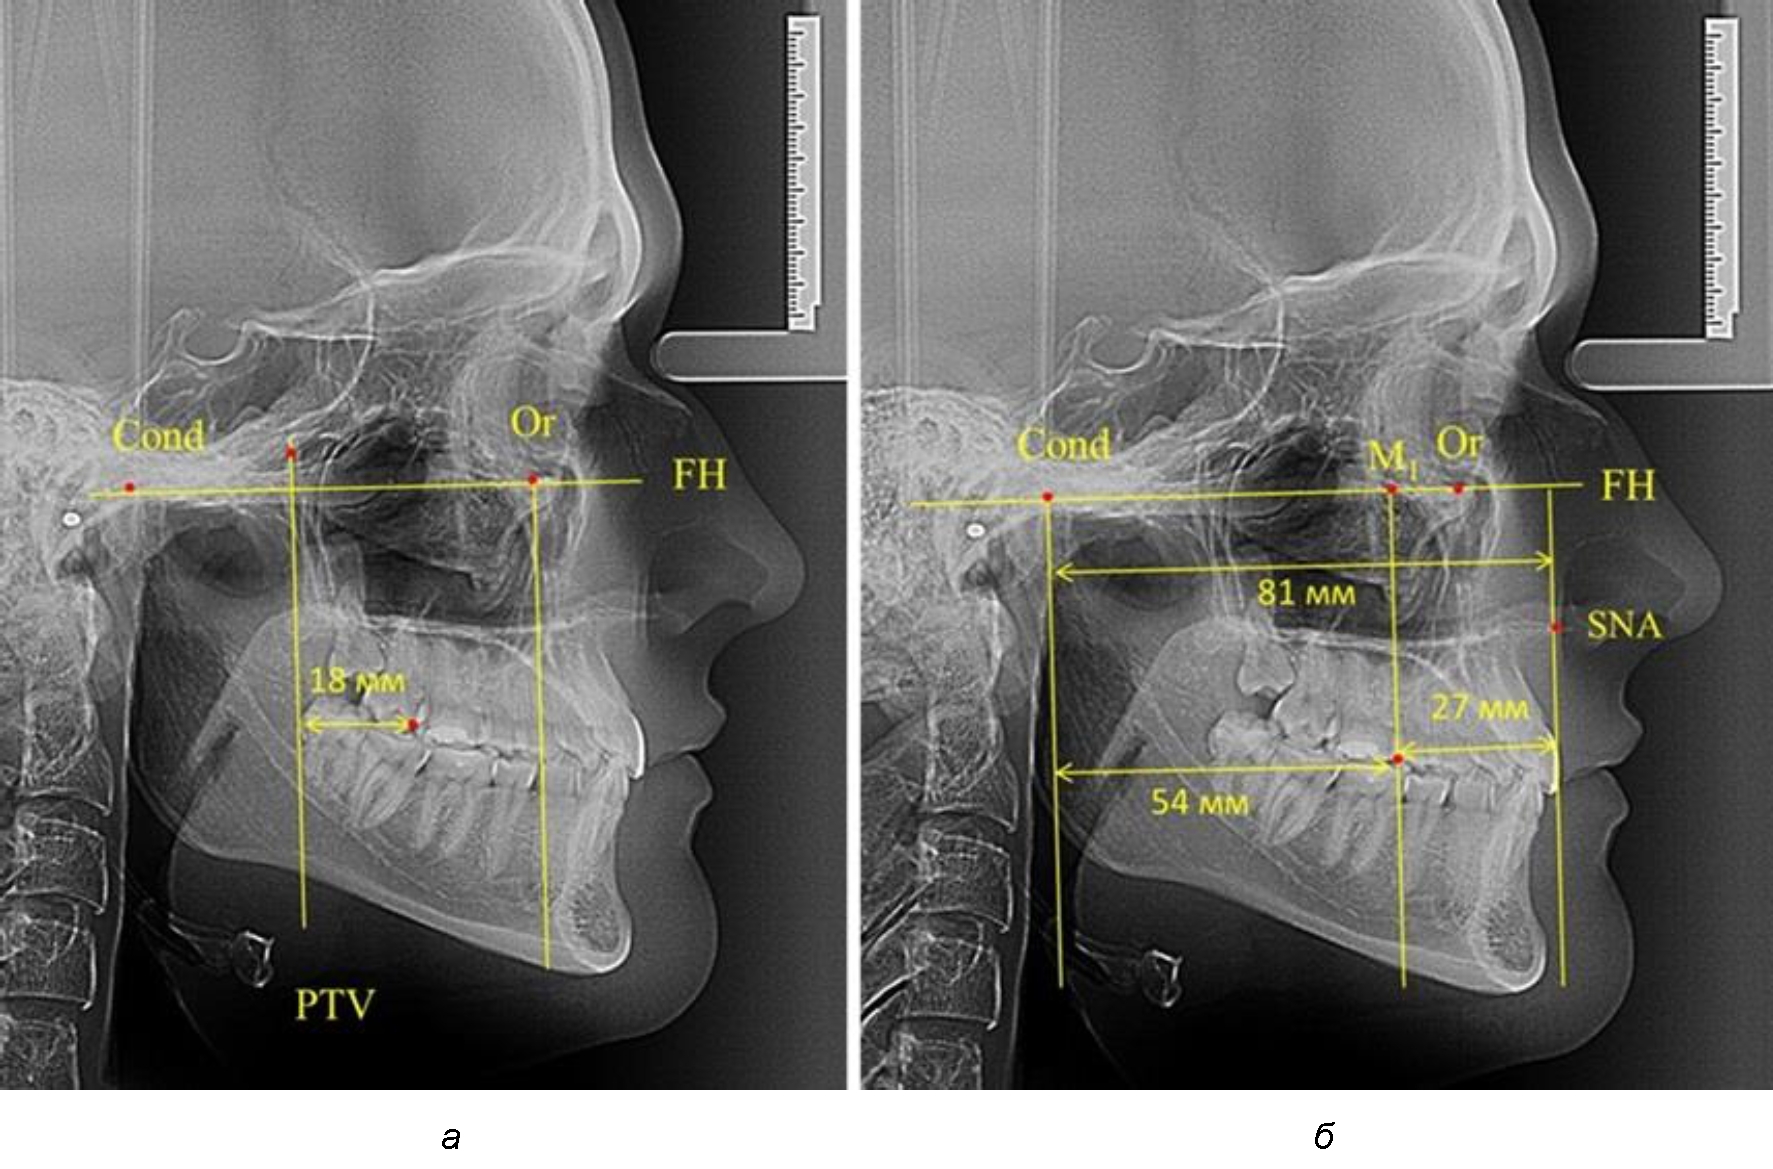

Рис. 1. Метод определения положения первых верхних моляров по Ralph E. McDonald (а) и по предложенному методу (б)

При проведении анализа к Франкфуртской горизонтали проводили передний и задний перпендикуляры. Передний спинальный перпендикуляр проходил через выступающую точку передней носовой ости (spina nasalis anterior – SNA), а задний суставной перпендикуляр опускали из кондилярной точки Cond. Молярный перпендикуляр проводили через медиальную поверхность первого постоянного моляра. Указанная вертикаль отделяла замещающие зубы постоянного прикуса от добавочных зубов (постоянных моляров), что вполне логично для анализа положения первых постоянных моляров в гнатическом комплексе (рис. 1).

Согласно указанному методу на рентгенограммах проводили Франкфуртскую горизонталь. Учитывая мнения специалистов относительно ориентиров для построения и вариабельность положения наружного слухового прохода, в качестве задней точки использовали верхнюю выпуклость суставной головки нижней челюсти («Cond»). Передняя точка традиционно располагалась на нижнем крае глазницы и определялась как орбитальная точка Or.

Находили положение точки Pt, которая располагалась на пересечении нижнего края круглого отверстия и задней стенки крыловидно-верхнечелюстной щели, и перпендикулярно к Франкфуртской горизонтали проводили крыловидную вертикальную линию, которую принято обозначать как плоскость PTV. Расстояние от крыловидной вертикальной плоскости PTV до дистальной поверхности верхнего первого постоянного моляра определяло его положение, которое, по мнению R. E. McDonald, соответствовало возрасту пациента, увеличенному на 3 мм.